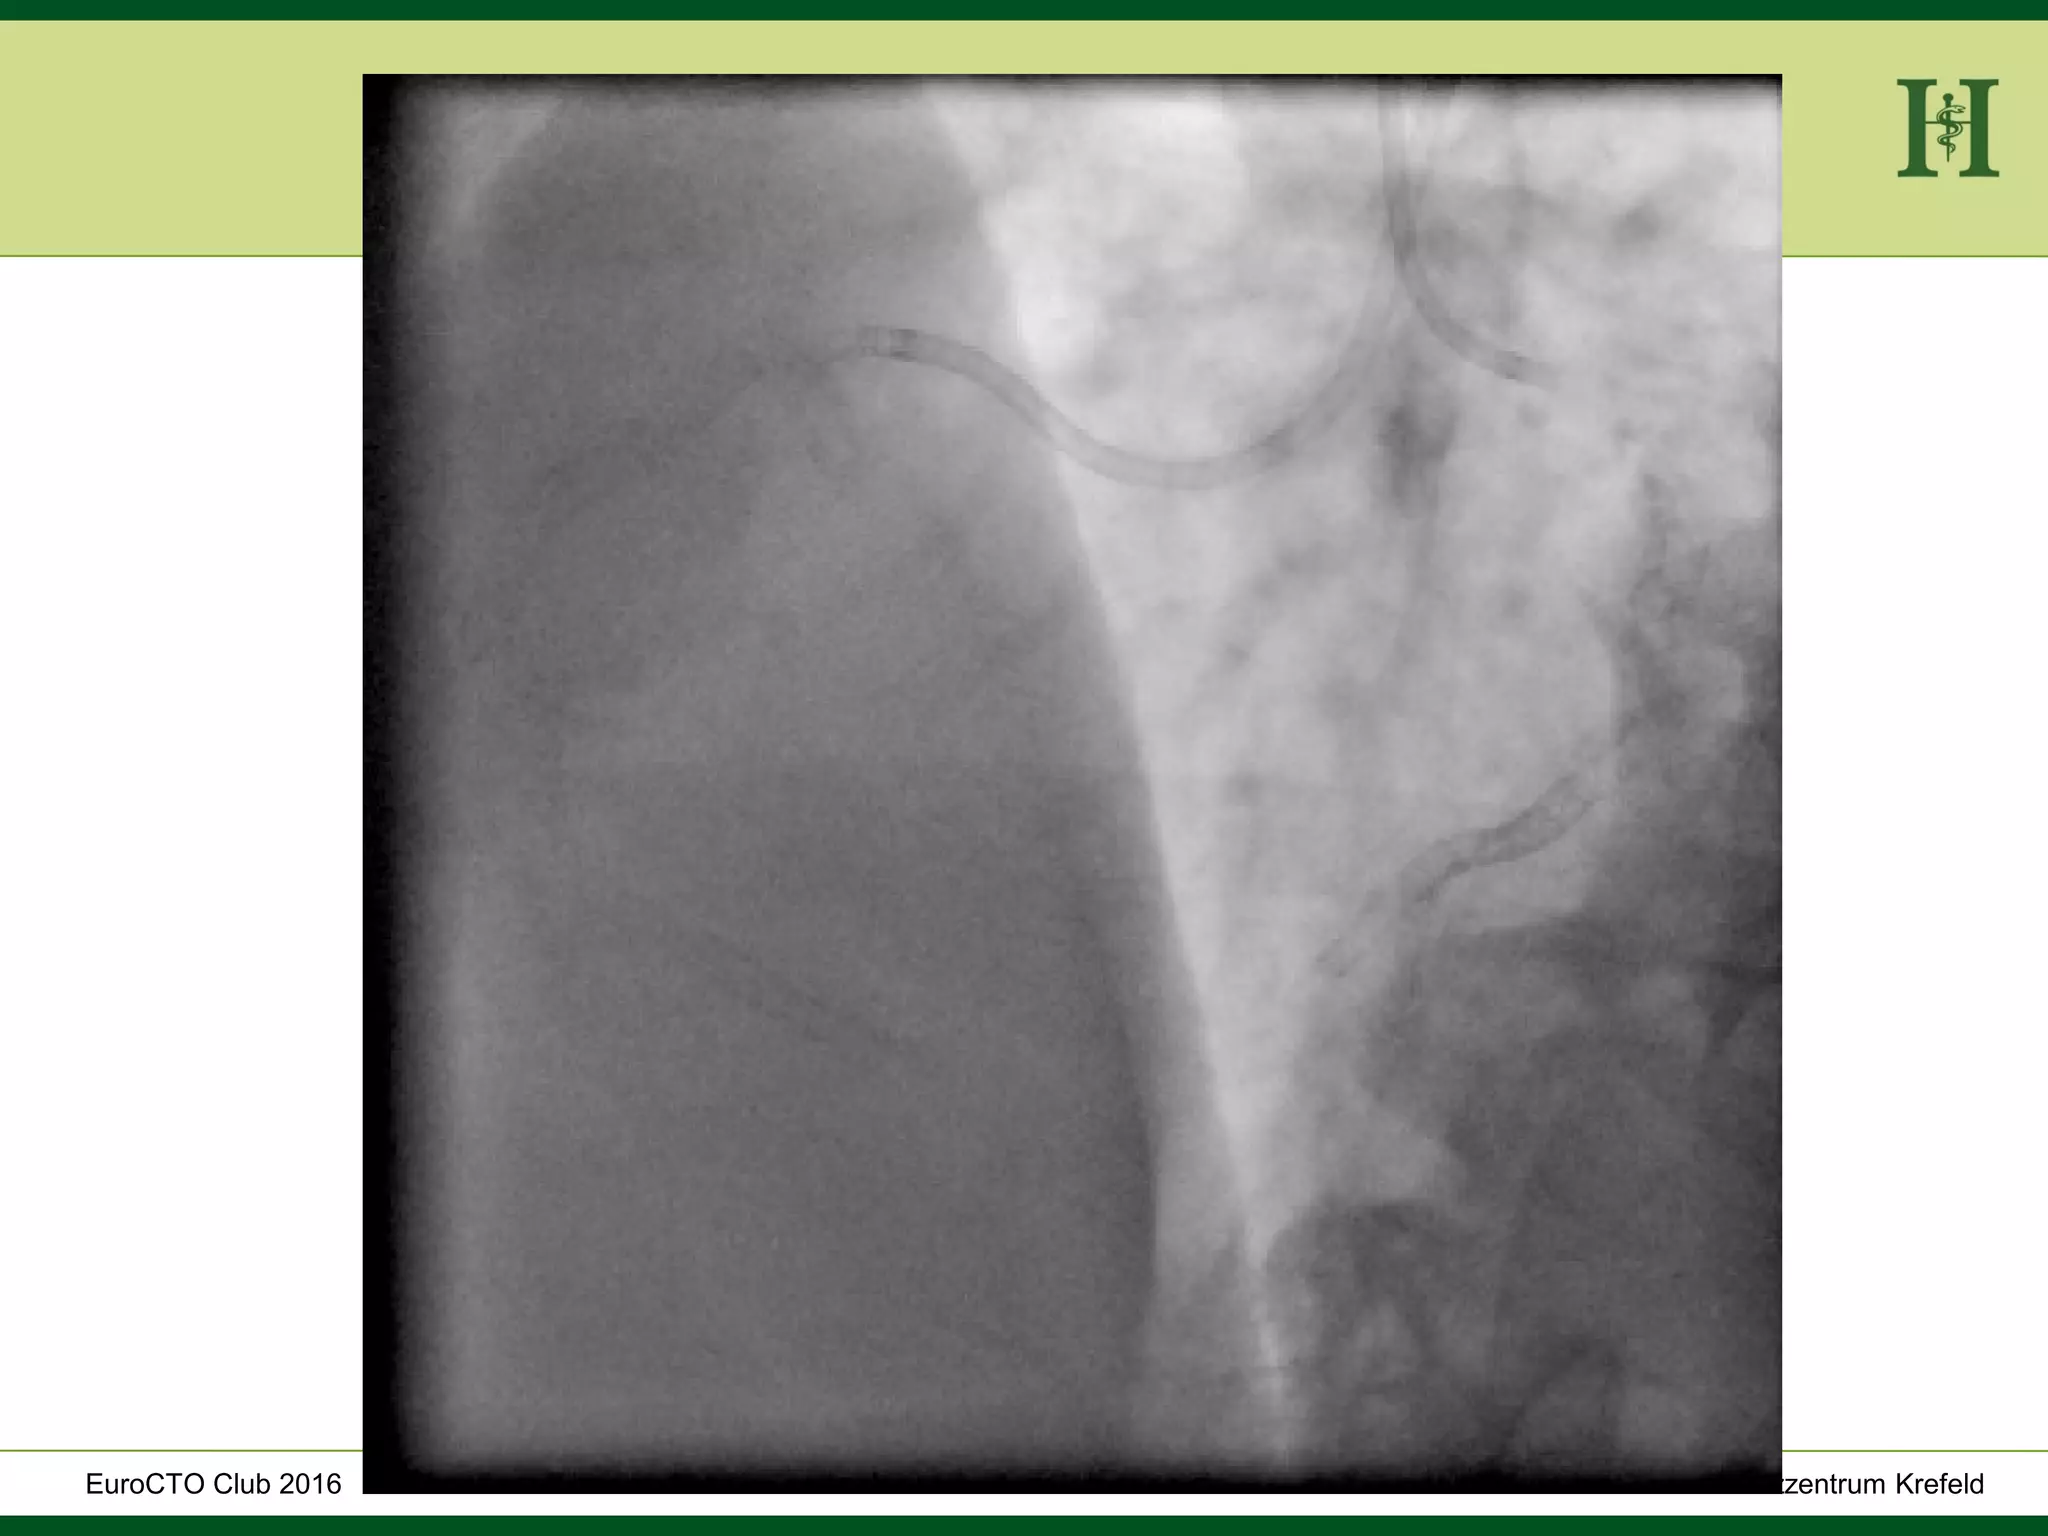

Male Patient, 55 years old

History:

 PCI 2015 with DES in LAD and in proximal RCA and

in PLD

 Angina pectoris CCS III for 7 months

 170cm, 75Kg

 RF: HLP, hypertension, smoking, HLP, familiy history

 Echo: Normal LV-Function, EF 65%

 Ischaemia inferior (MRI)